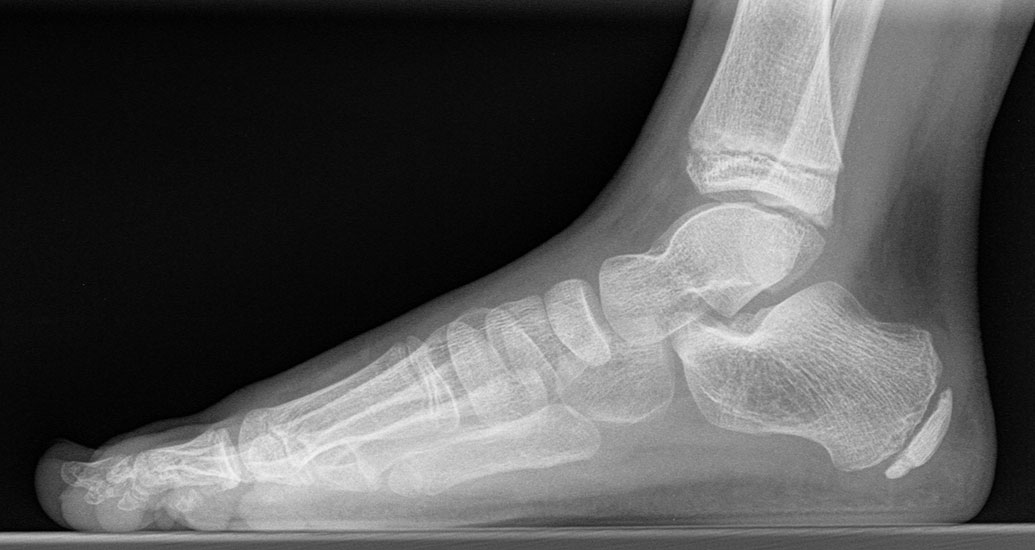

Standard ist die belastete Röntgenaufnahme des Fußes dorso-plantar und seitlich. Günstig ist eine Röhrenkippung von 10°-20°, um die Gelenke der Lisfranc-Linie einsehen zu können.

Ergänzend kann eine Schrägaufnahme hilfreich sein. Bei Metatarsalgien oder Pathologien der Sesambeine liefert die Sprinteraufnahme zusätzliche Informationen. Bei einer Pes planovalgus Fehlstellung wird ergänzend ein Saltzman view durchgeführt.

• Elevation/ Plantarisierung I. Strahl

• Pes metatarsus adductus